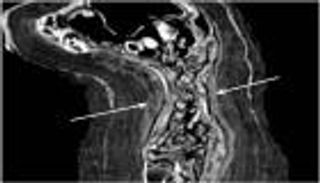

وأضافت: "الحالة الأولى كانت لرجل في الأربعينيات من عمره، ينتمي لطبقة كبار الموظفين، حيث أظهرت عظام ساقه اليمنى (القصبة والشظية) آثار بتر واضح مع التئام جيد للعظام، ما يدل على أنه عاش فترة طويلة بعد العملية. ونُرجح أنه استخدم رباطا أو طرفا صناعيا بدائيا لمساعدته على الحركة".

أما الحالة الثانية، بحسب د. باشا، فكانت لرجل عامل يتراوح عمره بين 40 و45 عامًا، أظهرت عظام ساعده الأيسر آثار بتر في عظمتي الزند والكعبرة، والعظام كانت ملتئمة بشكل جيد، وهو ما يعكس حصوله على رعاية طبية بعد العملية. كما لاحظنا وجود تشوه في عظم العضد، مما يشير إلى أن المريض استمر في استخدام ذراعه بعد البتر.